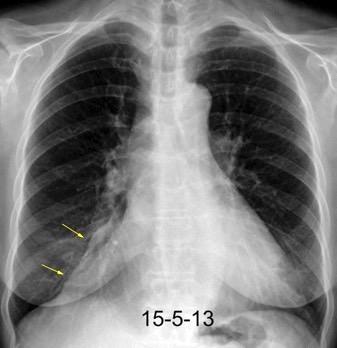

Linfoma de amigdala tratado diez años antes

Linfoma de Hodgkin..10

Linfoma no Hodgkin…2

Carcinoma.................... 7

Visualización en 21 casos

Positivo................6 (35%)

Dudoso.................3

Negativo..............8 (47%)

Vock. 1986.